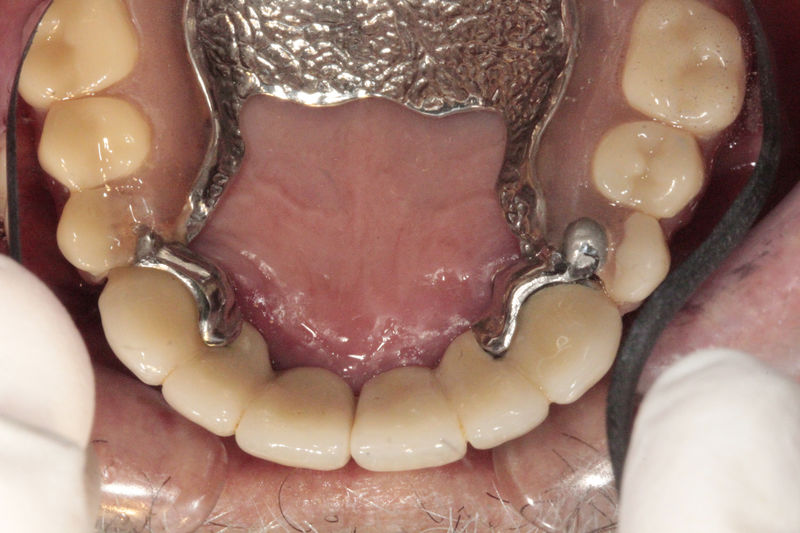

Restauraciones fabricadas en el laboratorio los cuales se usan para reemplazar dientes ausentes usando dientes, coronas y/o tejidos blandos como soporte y que pueden y deben de ser removidas para su limpieza. Para poder enviar el caso al laboratorio se toman impresiones utilizando materiales de impresión o técnicas modernas digitales.

Restauraciones fabricadas en el laboratorio los cuales se usan para reemplazar dientes ausentes en toda una arcada usando implantes y/o tejidos blandos como soporte y que pueden y deben de ser removidas para su limpieza. Para poder enviar el caso al laboratorio se toman impresiones utilizando materiales de impresión o técnicas modernas digitales.